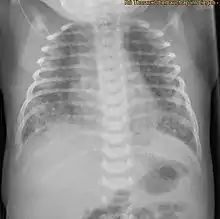

| X-ray showing the extent of lung epithelial damage in response to meconium seen in neonates with meconium aspiration syndrome. | |

Apoptosis is an important mechanism in the clearance of injured cells and in tissue repair, however too much apoptosis may cause harm, such as acute lung injury. Meconium induces apoptosis and DNA cleavage of lung airway epithelial cells, this is detected by the presence of fragmented DNA within the airways and in alveolar epithelial nuclei. Meconium induces an inflammatory reaction within the lungs as there is an increase of autophagocytic cells and levels of caspase 3 after exposure. After 8 hours of meconium exposure, in rabbit foetuses, the total amount of apoptotic cells is 54%.[15] Therefore, the majority of meconium-induced lung damage may be due to the apoptosis of lung epithelium.[1]